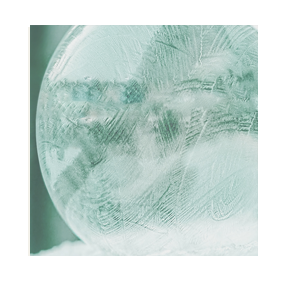

Testing – the ice ball forms around the probe

This creates a large ball of ice that engulfs the tumor. By alternating freeze and thaw cycles, the cells in the tumor are destroyed. By the end of the procedure there should be no viable cancer cells left. The progress of ice ball development is closely monitored throughout the procedure to ensure safety.

The cycle is activated and an iceball forms around the tumor. The freezing temperatures destroy the tumor tissue